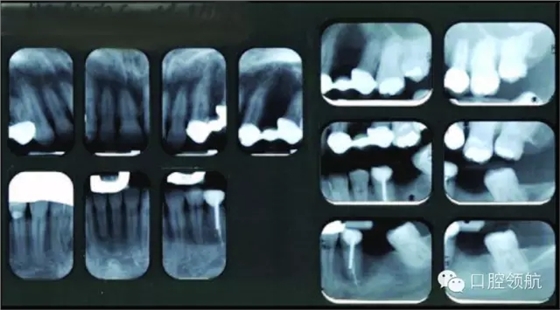

● 未見明顯的松動(dòng)度或者創(chuàng)傷牙合(圖3)。

圖3 上頜左側(cè)后牙的影像學(xué)檢查。